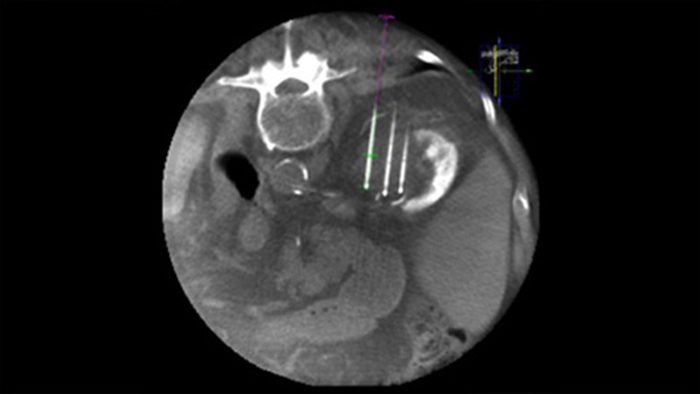

経皮的アブレーション(高周波、マイクロ波、およびクライオアブレーション)は、腎臓、肝臓、肺、および骨腫瘍の低侵襲治療として確立されてきています。腫瘍の境界を定義し、最適なニードルの数と対応するニードル軌道を決定して、よりよい腫瘍焼灼治療を実施し、周囲組織の損傷を引き起こさないようにすることが重要です。

Dual Viewでは、手技中3D CBCT Dual上に術前3D画像(CT/MR/PET-CT)をオーバーレイして、病変の視認性を高め、ニードル計画に必要な重要情報にアクセスできます。

XperGuideでは、事前計画した軌道を透視画像にオーバーレイ表示することで、各ニードルの高精度のライブイメージガイダンスを必要な位置に表示できます³。